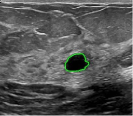

4.5 Comparison with breast ultrasound images segmentation

Unlike MR images mentioned above, ultrasound images offer real-time imaging but usually have lower resolution and contrast, making it difficult to differentiate between adjacent tissues and often introducing artifacts and noise that complicate segmentation. However, the RefLSM is robust to high levels of noise and intensity inhomogeneity, regardless of the type of medical image. To validate this, we perform segmentation comparison experiments on breast ultrasound images and calculate the Dice coefficient and Precision values for all models under evaluation.

In Fig. 10, the 1st row displays original images and initial contours for the RefLSM, while the second row shows the RefLSM’s segmentation results. Even with high levels of noise and severe intensity inhomogeneity caused by acoustic shadowing and motion artifacts, our model successfully identifies object edges, achieving an average Precision value of 0.9812. Table 4 shows that the RefLSM requires no more than 10 iterations and has an average processing time of only 1.79 seconds to segment images in Fig. 10.

To further validate the effectiveness of our model, we compared it with the ICTM, RESLS, and ALF models, represented in the 2nd, 3rd, and 4th rows of Fig. 11, respectively. The 5th row displays our proposed model. To better compare the segmentation results, we presented the initial contours in the 1st row, and the ground truth in the 6th row. We can observe that the ALF model struggles with boundary identification and has significant misclassification due to the boundary confusion in ultrasound images commonly caused by overlapping of soft tissues. While the ICTM and RESLS models perform well in some cases like column 1,4, and 7, they still face under-segmentation and over-segmentation problems when images are low contrast or have complex edges like column 1, 3 and 5. In addition to visual comparisons, we calculated the Precision and Dice coefficient for each model, as shown in Table 2. Clearly, the RefLSM outperforms all the other models in terms of mean score. Based on these results, we draw Fig. 12 to present the data distribution and facilitates comparison of different models’ performance across various breast ultrasound images. Although the ICTM model shows relatively close performance, it has nearly double the computational cost of the RefLSM. Therefore,the RefLSM demonstrates excellent segmentation capability and efficiency when processing ultrasound images.